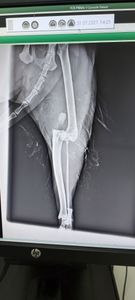

Boa noite. A gatinha de minha filha foi pega por um cachorro q causou luxação na sua pata traseira direita. Arrebentando todos os ligamentos, levei ela a um clínica veterinário q fez o raio X e contatou a fratura.

Me cobrando 3.500 para fazer a cirurgia, mais 350 já pago no cartão de crédito para a consulta e raio X.